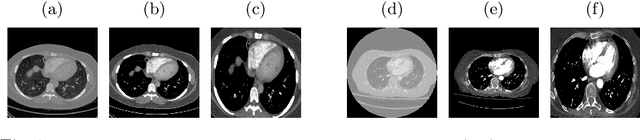

Abstract:Pulmonary embolism (PE) represents a thrombus ("blood clot"), usually originating from a lower extremity vein, that travels to the blood vessels in the lung, causing vascular obstruction and in some patients, death. This disorder is commonly diagnosed using CT pulmonary angiography (CTPA). Deep learning holds great promise for the computer-aided CTPA diagnosis (CAD) of PE. However, numerous competing methods for a given task in the deep learning literature exist, causing great confusion regarding the development of a CAD PE system. To address this confusion, we present a comprehensive analysis of competing deep learning methods applicable to PE diagnosis using CTPA at the both image and exam levels. At the image level, we compare convolutional neural networks (CNNs) with vision transformers, and contrast self-supervised learning (SSL) with supervised learning, followed by an evaluation of transfer learning compared with training from scratch. At the exam level, we focus on comparing conventional classification (CC) with multiple instance learning (MIL). Our extensive experiments consistently show: (1) transfer learning consistently boosts performance despite differences between natural images and CT scans, (2) transfer learning with SSL surpasses its supervised counterparts; (3) CNNs outperform vision transformers, which otherwise show satisfactory performance; and (4) CC is, surprisingly, superior to MIL. Compared with the state of the art, our optimal approach provides an AUC gain of 0.2\% and 1.05\% for image-level and exam-level, respectively.